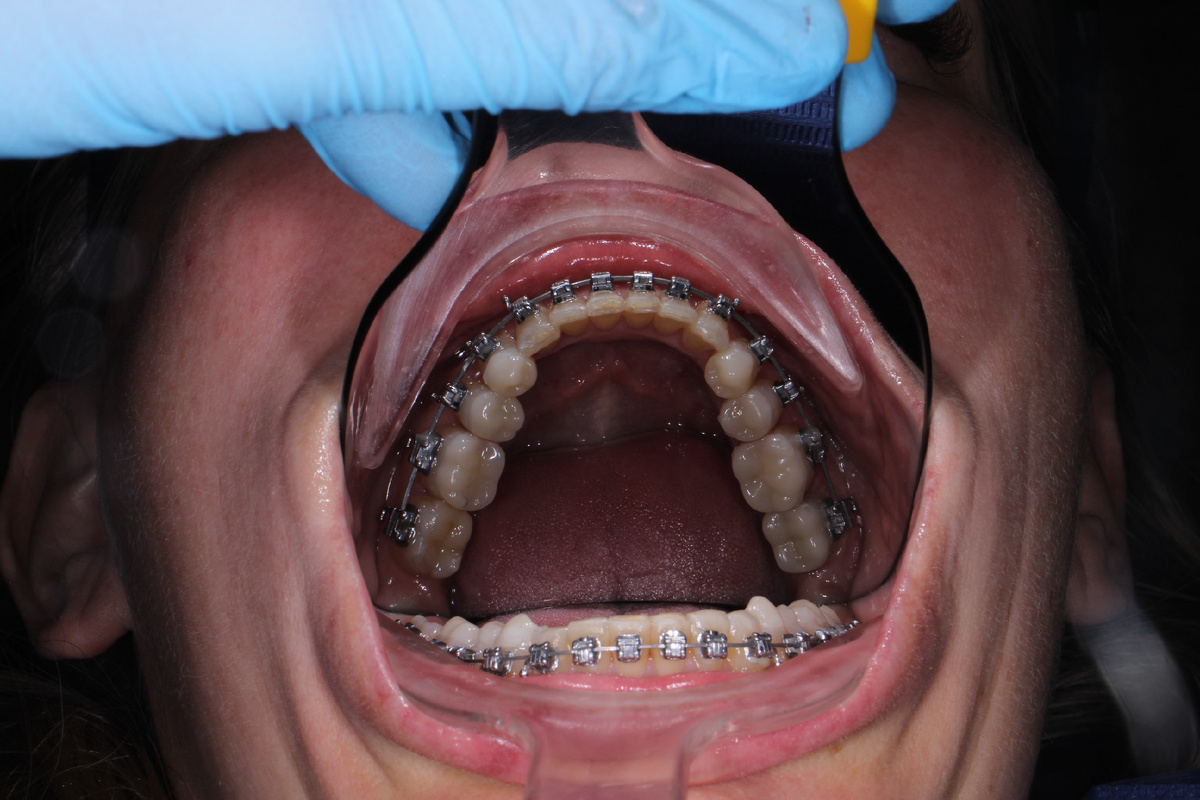

Главная задача накладок — это так называемая дизокклюзия, или, проще говоря разобщение прикуса. Зачастую, особенно в случаях глубоко прикуса если просто наклеить брекеты на нижние зубы сразу, то при смыкании челюстей ваши верхние зубы просто «собьют» нижние замочки. А если брекет выстоит под напором жевательного давления, то длительный контакт зуба с брекетом, особенно керамическим, приведёт к стираемости зуба. Оба варианта негативно сказываются на результате ортодонтического лечения.

Накладки создают временную «опору», которая не дает до конца сомкнуть зубы тем самым предотвращая контакт между брекетом и зубом, значительно снижая риск отклейки замочка.

Кроме того, когда мы разобщаем прикус зубы, особенно сильно дистопированные получают свободу передвижения. Без этого разобщения зубы будут биться друг об друга, сопротивляясь перемещению, и лечение затянется на годы.

Бывают и передние накладки, которые ставятся на небную поверхность передних резцов. Они выглядят как маленькие площадки или ступеньки, в которые упираются нижние резцы. Такие накладки используются для лечения глубокого прикуса, когда нам нужно, чтобы задние зубы «прорезались» чуть выше и подняли высоту лица.